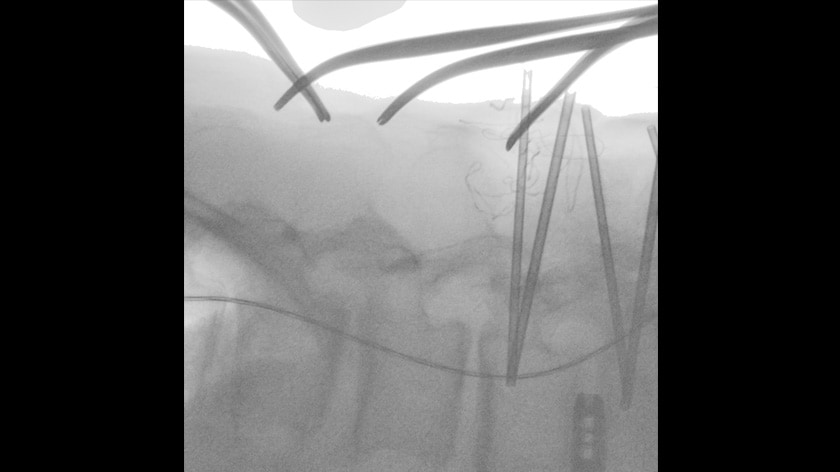

Manually operated flexible C-arm

The C-arm can be moved without releasing the lever lock. The counterbalance system enables C-arm fully manual operation including vertical movement. The C-arm lock can be released by one button for each direction with all electromagnetic controls. Buttons color-matched to the direction of movement of the C-arm are located at each side of the C-arm unit for intuitive operation.

Operable C-arm from the doctor’s side

Fluoroscopy image view position can be easily adjusted by the doctor. The doctor handle enables a doctor to perform the C-arm positioning and turn the laser pointer ON/OFF for speedy surgery.